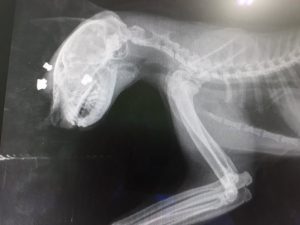

Fino a quando «la settimana scorsa dopo due/tre sere che non veniva a mangiare mi sono preoccupata e ho deciso di andare a cercarlo con la luce del sole. Ricerca inutile, sembrava scomparso nel nulla. Ma era assurdo che al suono della mia voce non arrivasse, di solito con quelle zampette corte e quel musino da birbante arrivava appena sentiva il rumore della mia auto. Rassegnata ho ipotizzato che qualcuno lo avesse investito e avessero gettato il cadavere nella spazzatura… Stavo andando via quando ho sentito un miagolio, un lamento, venire dal piazzale della farmacia. Entro nel recinto, ma è talmente flebile e ci sono cosi tanti rumori che non riesco a percepire da dove arriva». Dopo un pò, «inizia a miagolare più forte e senza smettere mi porta fino a una catasta di pedane. E finalmente lo vedo, è sotto una pedana, accovacciato in un angolino e talmente spaventato che quando provo a prenderlo, invece di scappare come avrebbe fatto un qualsiasi gatto randagio, si accartoccia su stesso e si affida a me. Gli guardo il viso e in un nano secondo è già nel trasportino e corro come una pazza dal veterinario. Lo hanno massacrato con un fucile ad aria compressa, hanno mirato sempre alla testa, i piombini gli si sono conficcati nel cranio, uno gli ha trapassato l’occhio, gli hanno dovuto aprire anche il palato per toglierne altri».

Adesso «è completamente cieco perché anche all’altro occhio ha un ematoma interno che gli impedisce di vedere. Non so ancora se ritornerà a vedere, sto cercando uno specialista che lo aiuti».

Insomma, «c’è un pazzo – meglio sarebbe dire criminale – su via Maria Pia che ha ucciso tutti i gatti della zona. Io credevo che morissero investiti invece lui li ha sterminati tutti con il fucile ad aria compressa. Spara alla testa e, visto che può sparare un colpo alla volta, è evidente che al gattino a cui sono stati tolti quattro piombini (uno non è riuscito a toglierlo, per farlo dovrebbe aprirgli il cranio) li ha sparati in momenti diversi. È un pazzo, li fa morire lentamente».